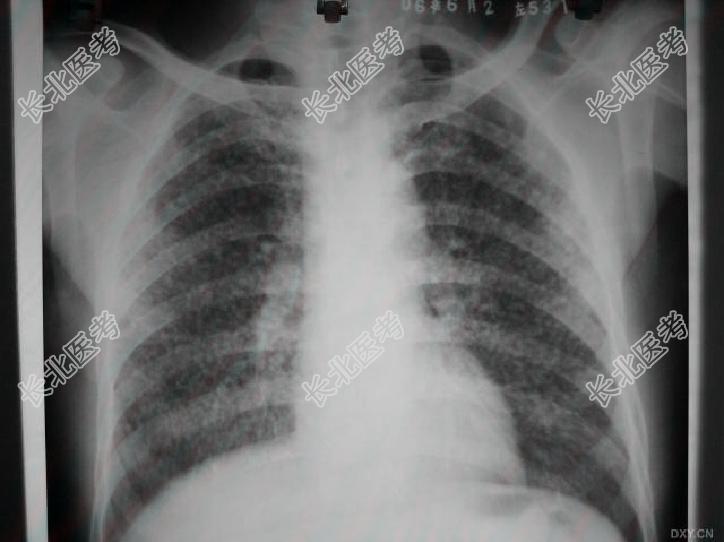

- 多项选择题1.提示:6月2日胸片(入院时胸片),见下图。

,